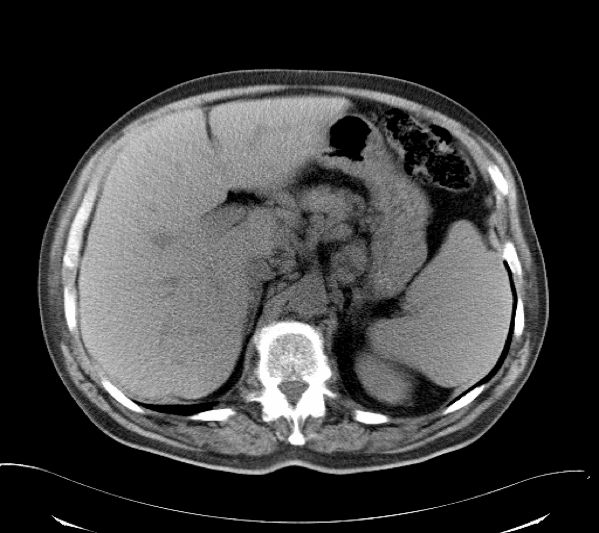

(软组织成像)

(超高分辨率成像)